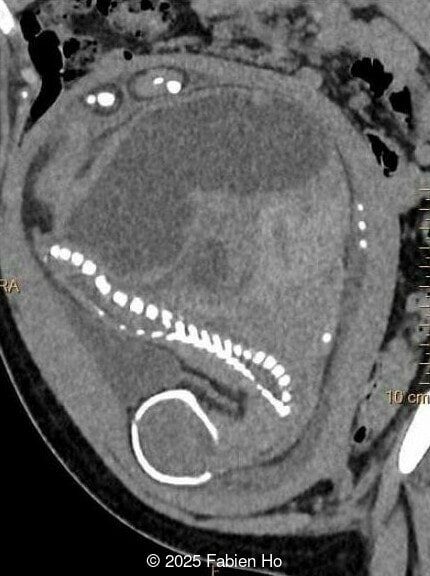

At 36 weeks gestation, the abdominal findings were unchanged however, the bones appeared short (<1st percentile) and the spine had an unusual appearance, therefore a computed tomography was performed at 37 weeks gestation.

Our prenatal ultrasound revealed a male fetus with megabladder, dilation of both ureter and kidneys, and thinned kidney parenchyma consistent with Lower Urinary Tract Obstruction (LUTO).  Additional findings suspected on ultrasound and confirmed on computed tomography included:

• Short long bones (<1st percentile), normal mineralization, and no sign of lethal chondrodysplasia

• Evidence of Potter's sequence due to the lower urinary tract obstruction with small thorax compared to the abdomen, hyperextended neck, and pes varus.

• Dysostosis: Hemivertebrae L3, fused L4-L5, abnormal left foot with short metatarsals and missing phalanges

• Suspicion of dilated bowel in the left flank, in addition to dilated urinary tract

The couple chose to deliver naturally. After prenatal needle aspiration of the bladder, the baby was delivered at 39 weeks gestation. Postnatal findings were consistent with Prune-Belly Syndrome with flaccid abdominal wall (similar to prune skin), lower urinary tract obstruction in a male fetus, imperforate anus requiring colostomy, lumbar hemivertebrae, and left foot hypoplasia including metatarsals and phalanges.